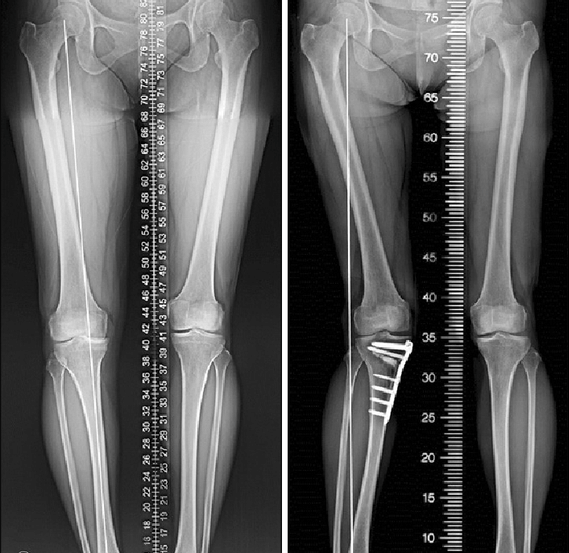

저는 전자 업체의 소형 부품 공장에서 거의 하루 종일 오가며 완성 부품 관리 또는 납품 사원으로 근무하다 47세 여성입니다. 1년 전부터 무릎이 조금씩 아프기 시작했다 약 8개월 전에는 무릎의 통증이 심해져서 병원을 찾아왔다. 병원에서는 무릎의 엑스 레이와 MRI을 찍고 보면, 반월상 연골판 손상(파열).깨지다)으로 무릎 뼈가 맞닿고 있어 무릎의 퇴행성 관절염 예방을 위해서 사전에 오다리 수술을 함께 가는 것이 좋다는 소견을 줬다. 아이들은 곳 곳에서 무릎 반월상 연골판 손상(파열).찢어진다)수술에 대해서 알아보니 과잉 치료하는 경우도 상당히 많아서, 대학 병원에서 진료와 상담을 받는 것이 된대요. 한번 반월상 연골판 수술(절제술)을 하면 재생되지 않아 무릎 반월상 연골판 수술을 받아도 무릎 수술을 잘하는 병원에서 최대한 반월상 연골판 절제술 외에 꿰매는 수술을 꼼꼼하게 하는 의사에서, 또는 반월상 연골판 파열 수술 없이 비수술적 치료에서 무릎 연골을 치료하는 것이 좋다고 하고 집으로 돌아갔습니다.

무릎 퇴행성 관절염 예방 및 비수술적 치료 분야와 반월상 연골판 파열 절제술이나 꿰매는 수술을 가급적 없이 치료하기로 유명한 대학 병원의 교수에게 검진을 받았더니 찢어진 반월상 연골판 손상(파열, 찢어진다?)부위를 관절 내시경에서 쉽게 정리하면 좋고, 오다리 수술은 전혀 필요 없다는 게 너무 안심했습니다. 양 무릎 안쪽 반월상 연골판이 조금 찢어져서 누더기가 되고 간단히 말하자면 부풀다만 정리하고 반월상 연골판 수술(시술?)은 아주 잘 끝나고 무릎 수술 후의 무릎 강화 운동(허벅지에 힘을 넣는 운동, 보행 보조기 걸음 등)무릎을 꺾는 등도 모두 완벽하게 끝냈습니다. 약 2주일 정도 입원해서 퇴원했는데 병원에서 받은 진통제를 마시면서 이제 1주일 집에서 쉬고 직장에 복귀했습니다. 그러나 문제는 그 다음부터였습니다.반월상 연골판 수술(관절 내시경을 이용한 수술)도 잘 갔고 무릎 굽히기나 무릎의 강화 운동도 충분히 했다고 생각했지만 막상 일상 생활, 직장 생활을 시작하자 무릎의 통증이 금방 재발했습니다. 옛날만큼 심한 통증이 없었지만 그 때보다 오히려 발에 힘도 들지 않은 느낌으로 무릎 통증의 원인이 전혀 알지 못하고, 어떻하면 좋을지 엄청 고민했습니다. 이런 이야기를 친척이 모인 3년 전의 조카 결혼식 식사 자리에서 나누던 중, 이모가 그것까지는 제가 몰랐던 미국의 의사들이 허리, 다리, 발, 무릎 퇴행성 관절염 예방 및 무릎 반월상 연골판 수술 등 무릎 수술 후 회복, 무릎 강화 운동 처방하는 세계적인 기능성 편안 구두 미국 전문 RX, 코일에 대해서 이야기를 들려주었습니다.